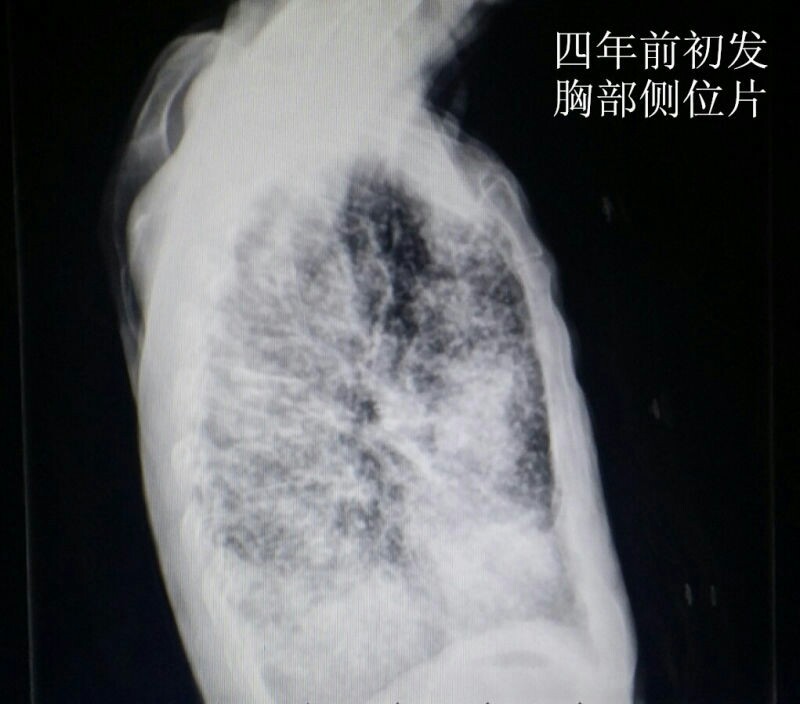

男性青年,未婚。 主诉:咳嗽数月,发现血尿三天。 现病史:患者半年前出现咳嗽症状,自服“消炎药”可减轻,一直未愈,近来加重。右腰背部偶感不适。发现终末血尿三天。患者自述近来消瘦、乏力。精神可,饮食可,睡眠好。 既往史:患者四年前因粟粒性肺结核就诊于当地结核病医院,给予口服抗结核治药物治疗(具体药物不详),后复查未见明显异常。 个人史:吸烟十年。 婚育史:未婚。 家族史:父母体健,无遗传病史。 实验室检查:肌酐:200umol/L(59-104) 尿素:10.4umol/L(2.86-8.2) 本院非结核病防治医院,无结核相关实验室检查。其余检查无阳性发现。 影像学检查(见插图): 1.四年前胸部平片及CT显示:双肺密布粟粒样结节,考虑肺结核。 2.现在胸部CT示:右肺尖及双肺背侧可见片状不规则高密度影,右肺中叶见厚壁空洞。考虑空洞型肺结核。 3.现在行腹部立位平片及CT示:右肾呈高密度团块状,结合病史考虑肾自截。 4.为进一步明确分肾功能,行核素肾动态显像示:右肾未见明显血流灌注,右肾未见明显显影,右肾功能重度受损,右肾肾图呈低水平延长线性改变。左肾功能大致正常。 诊疗经过:鉴于右肾无功能,行右肾摘除术(送病理,回报:肾结核)。请胸外科会诊,建议转入胸外科行肺段切除术。目前右肾摘除术后。 小结:近年来结核病例有上升趋势,尤其是肺结核。本病例类似的情况较少见,特此分享供大家学习。